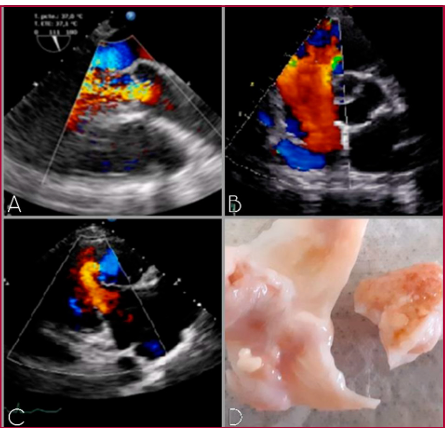

Tratamiento quirúrgico de enfermedad carcinoide cardíaca: reporte de casos